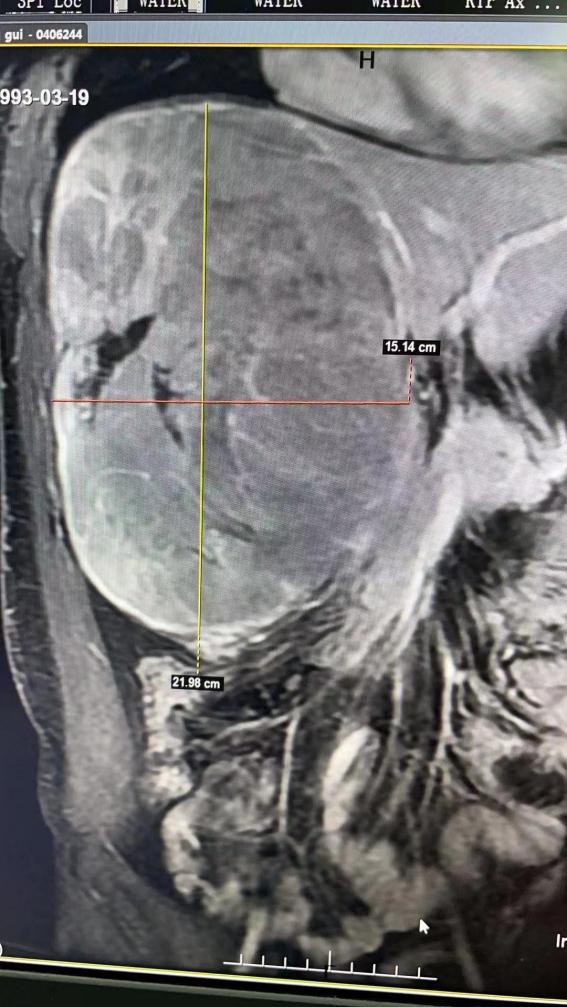

29歲的小黃,近段時間總感覺右上腹脹脹的,人沒力氣,胃口差,一下子瘦了七八斤。年輕力壯的他本想扛著,但家人知道后,強拖著他到當?shù)乜h醫(yī)院就診,正是這一次就診經(jīng)歷讓他和家人感到了前所未有的絕望。原來小黃是乙肝病毒攜帶者,一直未在意。這次腹部增強CT檢查發(fā)現(xiàn),右肝長著21×15×13 cm,如哈密瓜般大小的巨塊型肝癌。由于瘤體巨大且臨近重要血管和膽管,當?shù)蒯t(yī)院稱手術(shù)難度極大、風險極高,建議去南昌、上海的大醫(yī)院治療??烧敌鹿谝咔榱餍?,外出就醫(yī)困難,經(jīng)過多方打聽,小黃抱著最后一絲希望來到我院就診。

普外科主任丁金火認真查看影像資料及血清學化驗結(jié)果,發(fā)現(xiàn)主要瘤體位于右半肝,已經(jīng)壓迫肝門重要管道及鄰近組織器官,化驗血甲胎蛋白(AFP)正常,異常凝血酶原(DCP)超過20000ng/ml(正常值<40ng/ml,AFP及DCP是原發(fā)性肝癌主要的血清標記物),肝癌診斷明確,且腫瘤巨大極易因外傷或自發(fā)破裂大出血,隨時有生命危險。丁金火立即安排小黃住院,由團隊肝腫瘤亞專科負責人洪波接手后續(xù)治療。